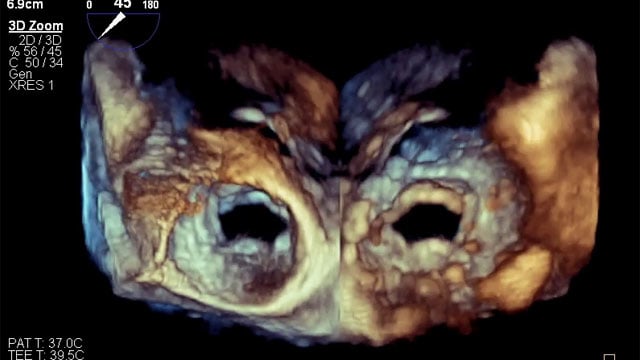

Severe MR in a high-risk patient with a suboptimal anatomy for M-TEER: what other options can we find?

Multimodality imaging reveals fibro-calcific leaflet disease, restricted motion, and a short posterior leaflet, making him a suboptimal candidate for M-TEER and prompting consideration of transcatheter mitral valve replacement. How would you treat?

M-TEER with Mitraclip Gen5

16 Feb 2026

An 83-year-old woman with HFrEF from NICM, hypertension, and persistent AF presents with worsening exertional dyspnea, severe functional MR, and moderate TR. How would you manage this patient?